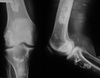

45

Name 4 major radiographic features on this radiograph.

- generalized osteopenia - widening of intercondylar notch - uniform jt space loss - ballooning of epiphysis

46

Give 2 differentials in order of likelihood. What 2 features support your diagnosis?

1. Hemophilia 2. JIA - ballooning of epiphysis - squaring of patella